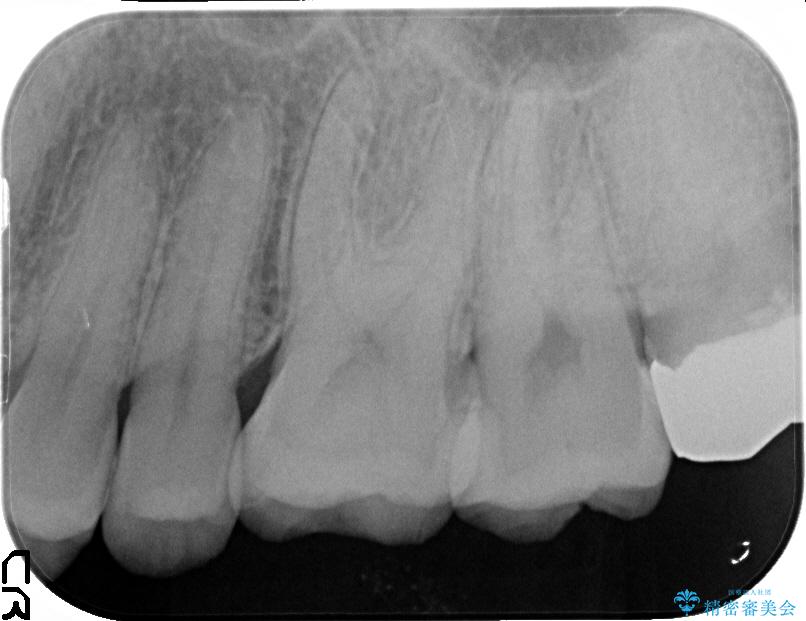

保険で治療した銀歯は、経年劣化で詰め物のふちが欠けたり、適合が悪くなり詰め物の下など目に見えない部分の虫歯の原因となることがあります。また、金属のため口にするものの熱の影響を受けやすく成分が溶けやすくなったり、変形してしまうことがあります。